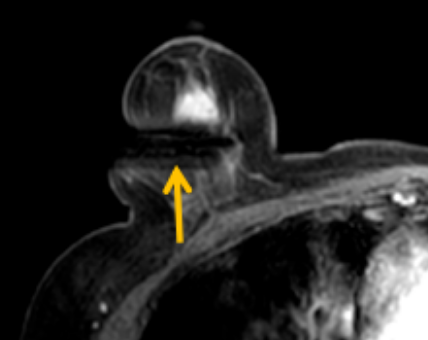

陳寶瑩評估圖像后發(fā)現(xiàn)病變?yōu)閮H僅在磁共振增強(qiáng)時(shí)顯示,為非腫塊樣病變,比較散,必須取得足夠多的組織才能確保病理檢查的準(zhǔn)確性,常用的核芯針活檢獲取的組織較少,因此最終確定了磁共振引導(dǎo)下行真空輔助抽吸旋切活檢。取得患者及家屬認(rèn)可后,陳寶瑩帶領(lǐng)團(tuán)隊(duì)開始進(jìn)行術(shù)前準(zhǔn)備。

針對患者乳房小固定難度大這一問題,陳寶瑩通過巧妙體位和固定器的調(diào)整,順利固定好乳房。經(jīng)過磁共振多模態(tài)掃描,陳寶瑩找出病變活性成分相對集中區(qū)域,精準(zhǔn)確定穿刺路徑,置入引導(dǎo)針、旋切針,到位后多角度旋切取出足量組織,拔除旋切針后即時(shí)行磁共振掃描,精準(zhǔn)取得組織且術(shù)區(qū)出血很少,遂加壓包扎,整個(gè)過程非常順利,旋切活檢后患者回家休息。兩天后隨訪,李女士沒有任何不適,五天后皮膚上幾毫米的小切口已經(jīng)愈合。最終病理結(jié)果證實(shí)為乳腺導(dǎo)管原位癌,為早期乳腺癌,為患者后續(xù)針對性治療奠定了基礎(chǔ)。